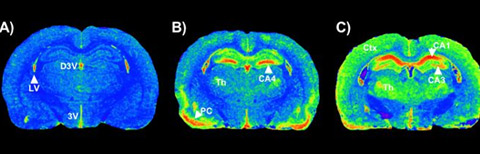

Cross-sectional autoradiograms of rodent brains showing (A) control physiological state; and (B) and (C) showing

distribution of brain injury from an injected neurotoxicant. Red areas indicate the highest concentrations of a

biomarker that identifies brain areas that are damaged by the neurotoxicant. Credit: Guilarte Lab

Cross-sectional autoradiograms of rodent brains showing (A) control physiological state; and (B) and (C) showing distribution of brain injury from an injected neurotoxicant. Red areas indicate the highest concentrations of a biomarker that identifies brain areas that are damaged by the neurotoxicant.